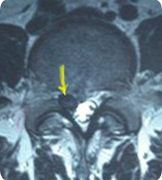

林先生磁振造影檢查有嚴重的第4-5腰椎間盤退化,並向後下方突出,壓迫了神經根,脊管內的脊髓液及神經。

磁振造影檢橫切面 可見突出的椎間盤,向後下方位移至第五 腰椎體後方

後註: 林先生的椎間盤突出並向下位移,是屬於內視鏡手術 中困難不易成功的病例,我們將突出的椎間盤全部取出,術後原有的症狀完全解除。林先生及本站其他感謝函,未經修改一字,全文刊登。